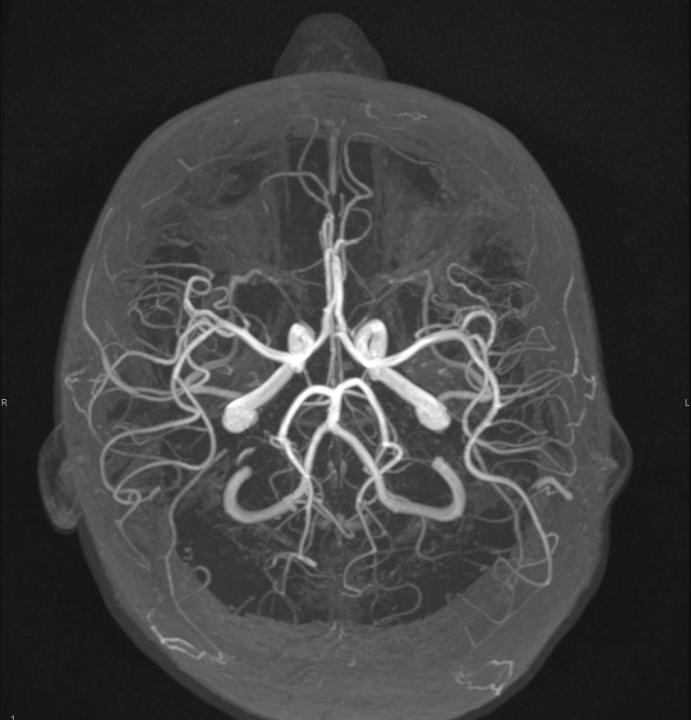

Tijekom Tjedna mozga Poliklinika Affidea Vita daje 20 posto popusta na magnetsku rezonancu!

Povodom obilježavanja Tjedna mozga od 11.

MR mozga

MR angiografija